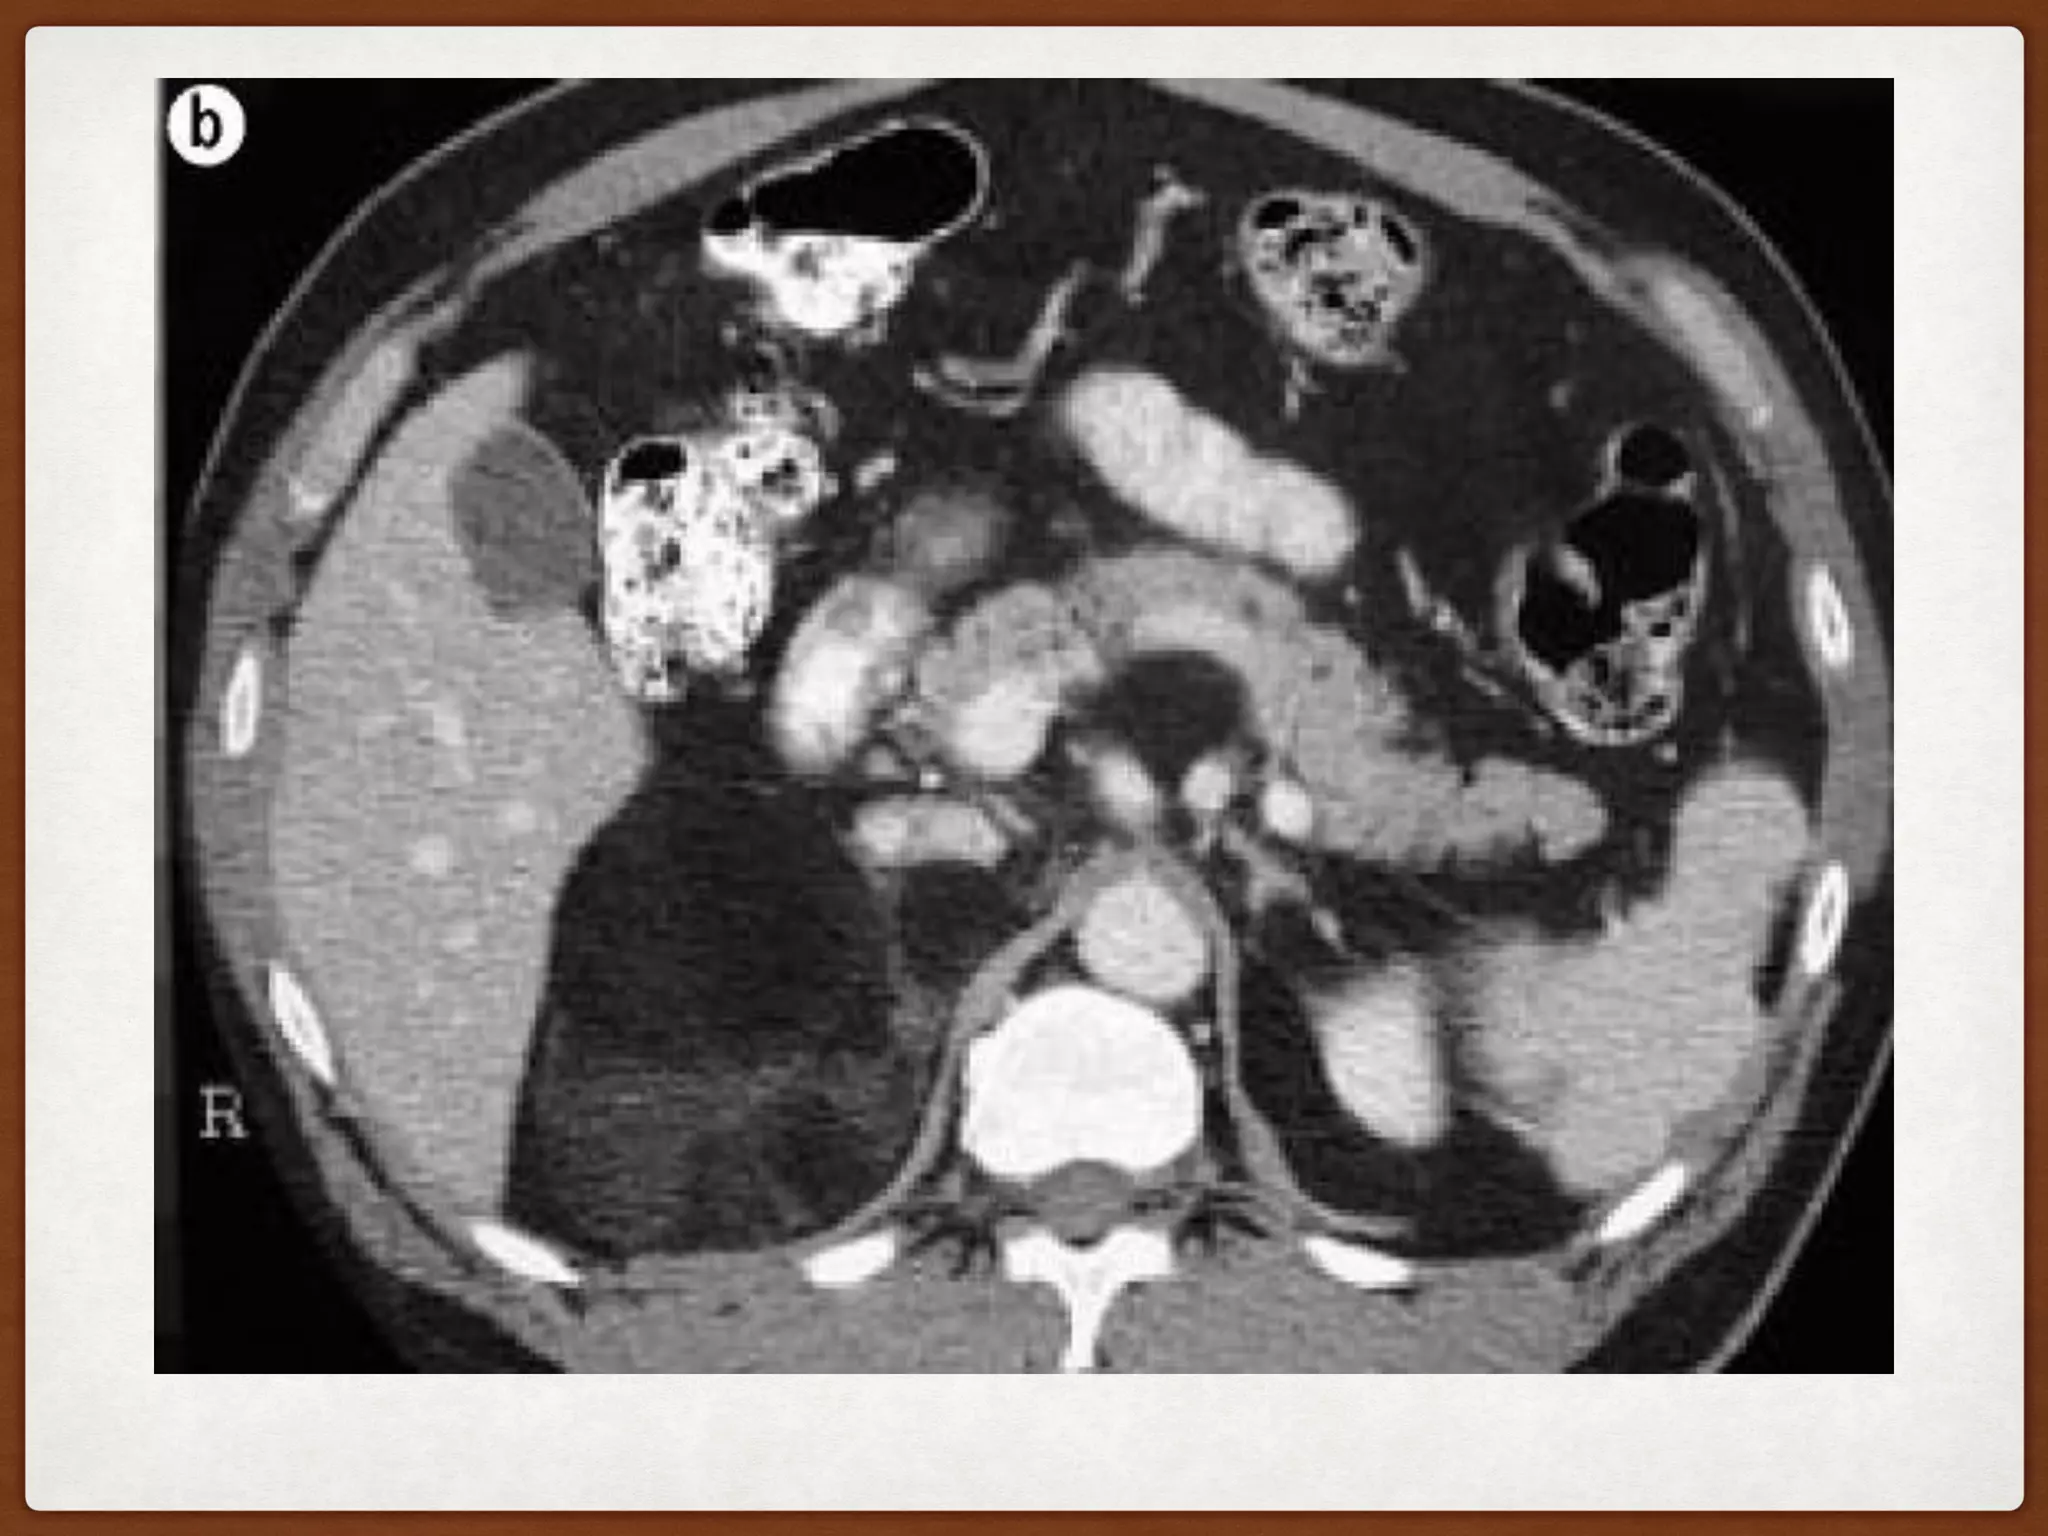

Figure : Adrenocortical carcinoma with liver metastases. CT axial image showing ill-

defined, infiltrative right adrenal mass (M), displacing the inferior vena cava

anteriorly (block arrow), invading right crus of diaphragm (black arrow) and

multiple liver metastases (white arrows). There is focal loss of fat planes without

any obvious infiltration of liver. The anterior displacement of inferior vena cava is

consistent with an adrenal mass.